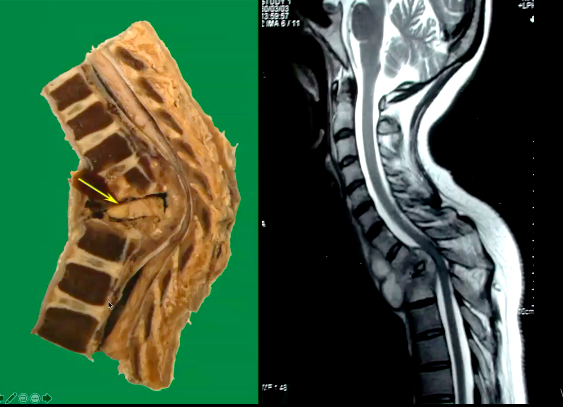

What pathology is shown?

Pericardial effusion from TB

Pott’s spine –> a form of TB where the bacterium infects the IV joints, charactersitically the infection starts in the IV disc, it spreads and can compress the spinal cord –> leads to neurological deficit.